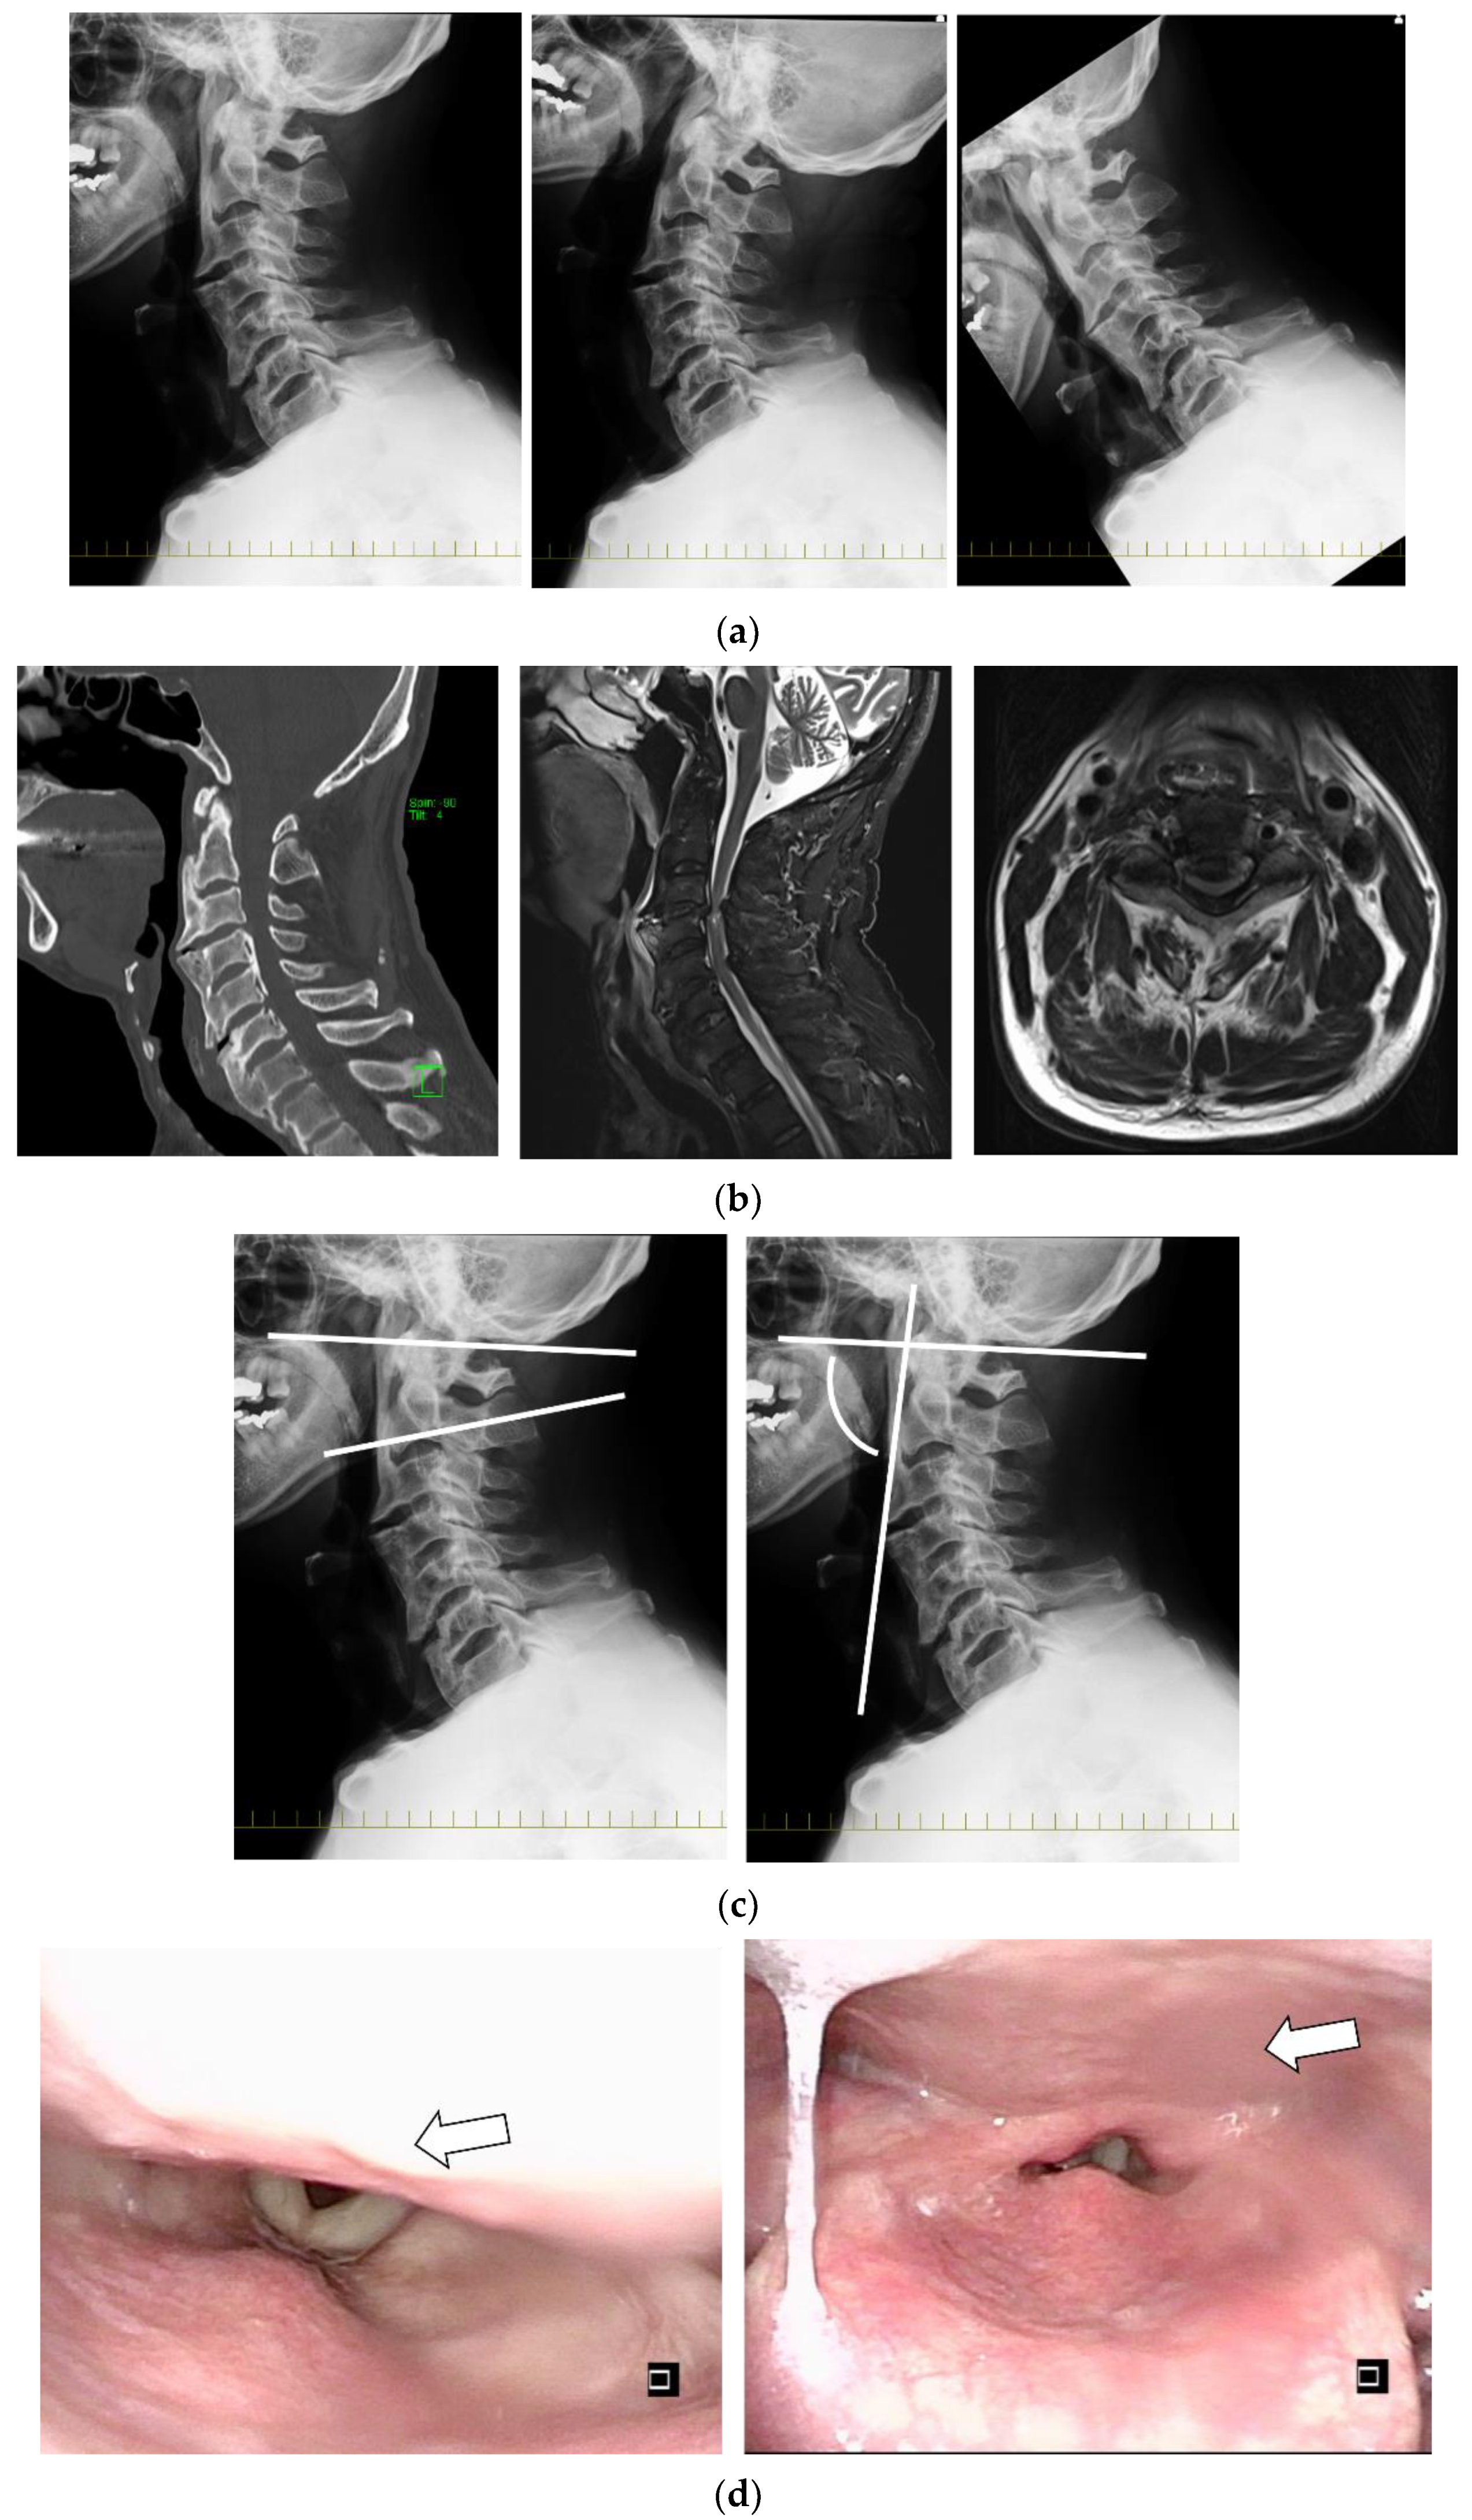

Ossification of the Anterior Longitudinal Ligament with Dysphagia as the First Symptom: Rehabilitation of Two Cases

2.5. Clinical Presentations